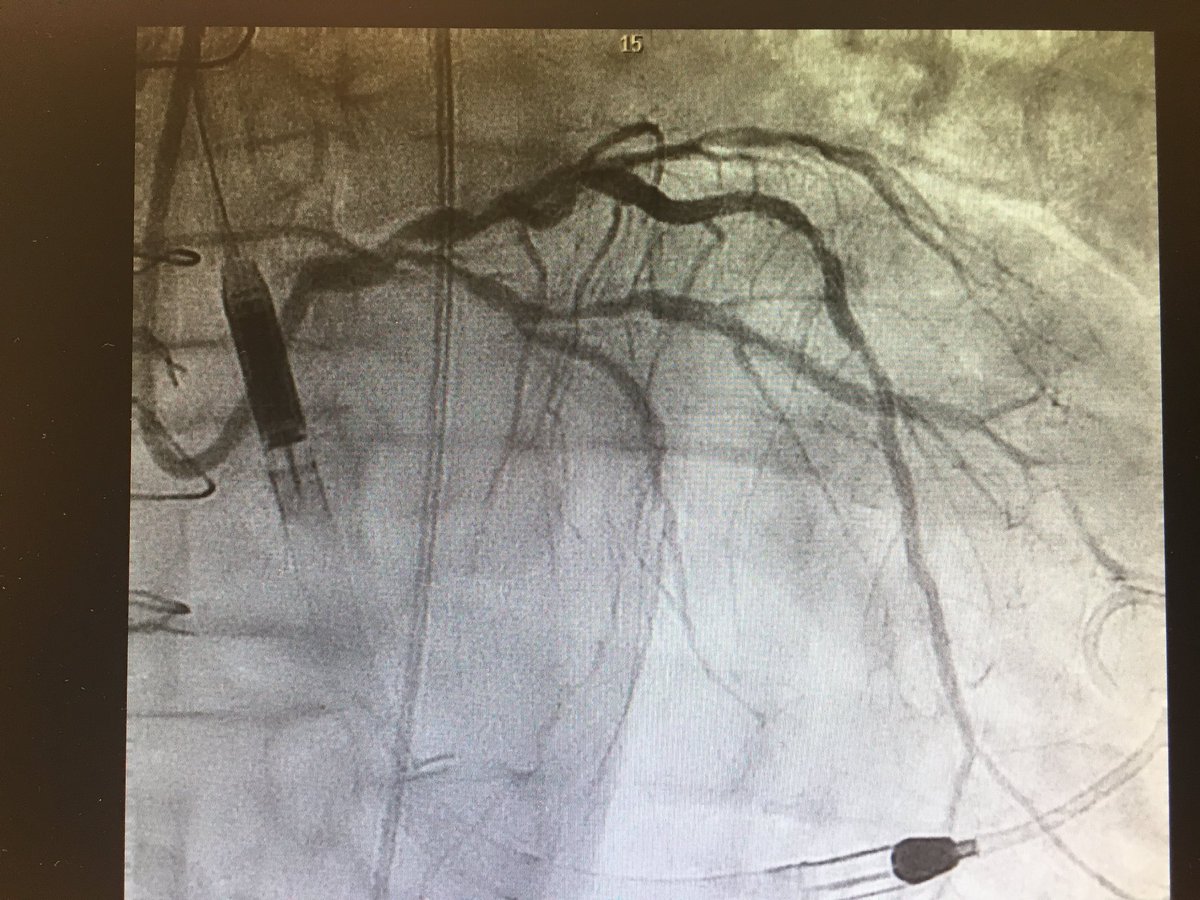

#CHIPcase 74yo male, LM+3vd, LVEF 17%, previous non-functionant CABG. Previous inferior MI without inferior viability. Actual NSTEMI with cardiogenic shock. Sent to our centre for Complex PCI @foroic @belcid7 @sbrugaletta @mmamas1973 @shci_sec @jedicath @hect2701 @Xavi_Carrillo7